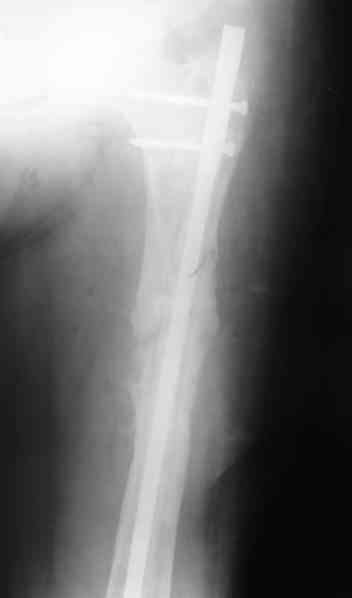

В качестве демонстрации лечения канального остеомиелита бедренной кости представляем пациентку (см. parts 2 и 3), которая как раз сегодня была у нас на контрольном осмотре. В мае этого года мы произвели ей фиксацию бедренной кости штифтом-спейсером по поводу ложного сустава и канального остеомиелита бедренной кости. Через 4 недели после операции свищи закрылись. Сейчас она ходит с полной нагрузкой на конечность.

4, 5, 6 - рентгенограммы бедра и фотографии пациентки (прошу прощения за низкое качество рентгеновских снимков) от 7 сентября 2007 г.